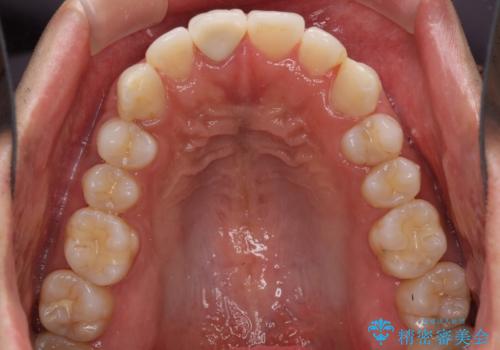

口が閉じにくい インビザラインによる矯正治療

- 口の閉じにくさを気にして来院された患者様です。

患者様と相談の上、横顔の印象から抜歯矯正は必要ないと判断し、IPR(歯と歯の間)並びに歯列全体の後方移動により口元の突出感の改善することとしました。

しっかりと装着時間を守り、ゴムかけも徹底していただいたので、思いの外口元を引っ込めることができました。

これ以上の改善を望まれましたが、非抜歯矯正でこれ以上口元を引っ込めると食いしばりすやすい咬合となるため、この歯列で終了としました。